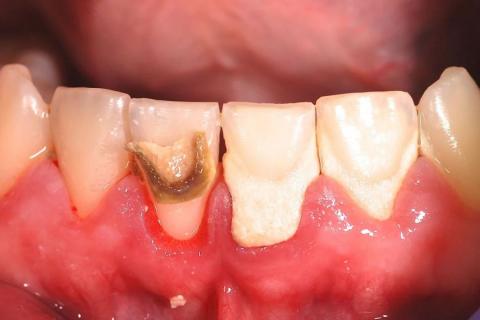

The image shows localized but advanced decay at the cervical (gum-line) and root surface of an anterior tooth, with adjacent teeth also showing gingival recession. The darkened area indicates dentin/root involvement, not surface staining. The gum tissue appears inflamed and recessed, exposing softer root surfaces that are highly vulnerable to rapid decay.

Deep Examination Findings (Image-Based)

Clearly demarcated carious lesion at the root surface

Loss of normal tooth contour near the gum line

Inflamed gingiva with reduced attachment height

Adjacent teeth show early risk due to recession